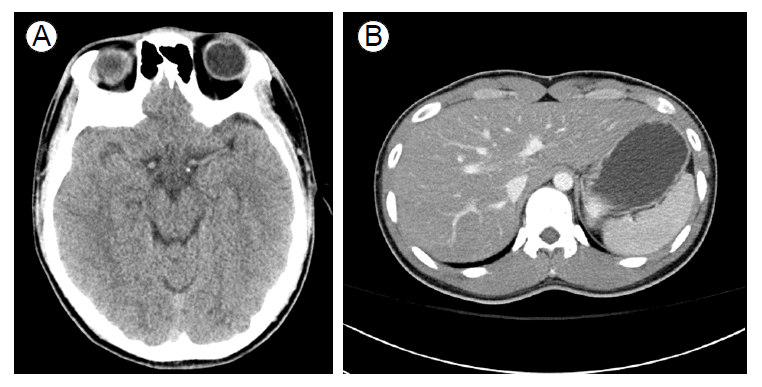

환 자: 19세, 남자주 소: Primaquine 과복용현병력: 평소 건강하던 환자로 의무병으로 군복무 중인 상태로 내원 1일 전 여자친구와 다툰 후 군부대에 있는 primaquine(15 mg) 40알을 복용하였다. 당시 타 병원 방문하여 위세척 및 활성탄 투약 후 추가적인 치료 위해 본원으로 전원되었다.과거력 및 가족력: 특이 소견 없었다.투약력: Primaquine 이외의 다른 약물이나 한약, 민간요법 및 보조식품 복용력은 없었다.이학적 소견: 내원 당시 급성병색을 보였으며 활력증후는 혈압 121/86 mmHg, 맥박 106회/분, 호흡 수 26회/분, 체온 36.8℃였다. 의식은 명료했고 신경학적 이상소견은 없었다. 두경부 검진상 공막 황달이나 결막 창백 소견은 없었다. 흉부검진상 심음은 빨랐으나 규칙적이었으며 잡음은 들리지 않았으며 수포음과 같은 이상 호흡음은 청진되지 않았다. 복부검사에서 우상복부에 간비대나 압통, 반발통은 관찰되지 않았으며 장음은 정상적이었다.검사실 소견: 내원 당시 시행한 말초혈액검사에서 백혈구 15,200/mm3, 혈색소 14.8 g/dL, 혈소판 288,000/ mm3로 백혈구 증가소견이 관찰되었다. 생화학검사상 크레아티닌 0.89 mg/dL, aspartate aminotransferase (AST) 19 IU/L, alanine aminotransferase(ALT) 14 IU/L, alkaline phosphatase 70 IU/L 총 빌리루빈 0.9 mg/dL, 직접 빌리루빈 0.5 mg/dL, 알부민 3.7 g/dL이었다. 프로트롬빈 시간은 98.9% (11.8초, INR 1.01)였다. 맥박산소계측기로 측정한 산소포화도(SpO2)는 86%였으며, COoximeter 상 산화헤모글로빈(O2 Hb) 83.2%, 메트헤모글로빈(Methemoglobin, MetHb) 14.7% (정상치: 0.4-1.5%)로 나타났다.방사선학적 소견: 흉부 단순 촬영상 특이 소견은 없었다.치료 및 경과: 환자는 primaquine 과복용에 의한 메트헤모글로빈혈증으로 진단하고 methylen blue 2 mg/kg을 5분간 정주하였다. 메트헤모글로빈혈증은 methylen blue 투여하면서 호전되기 시작하여 약물투여 3시간 후 시행한 CO-oximeter 상 산화헤모글로빈 91.2%, 메트헤모글로빈은 6.8%로 감소하였고 이후 12시간 가량 경과한 후 다시 측정한 메트헤모글로빈은 더욱 감소하여 3.2%로 나타났다. SpO2는 95% 이상으로 지속적으로 유지되었다.내원 2일째 환자는 안절부절 못하는 불안증세를 보이기 시작하였고 이어 환시, 착란 증상을 호소하였으며 이후 의식이 저하되며 기면(drowsy) 상태를 보였다. 의식 저하에 대해 신경학적 검사를 시행한 결과 국소 신경학적 결손을 시사할만한 소견은 보이지 않았으며 두경부 전산화 단층 촬영상에서도 이상 소견은 관찰되지 않았다(Fig. 1A). 당시 시행한 혈액검사상 AST 2,410 IU/L, ALT 2,505 IU/L, alkaline phosphatase 92 IU/L 총 빌리루빈 3.7 mg/dL, 프로트롬빈 시간 47.5% (18.3초, INR 1.55)로 간수치의 급격한 상승 및 프로트롬빈 시간 연장 소견을 보였다. 12시간 후 연이어 나간 검사 상에서는 AST 7,788 IU/L, ALT 7,456 IU/L, 총 빌리루빈 3.8 mg/dL, 직접 빌리루빈 2.4 mg/dL, 프로트롬빈 시간 35.6% (23.7초, INR 2.00)로 간기능이 더욱 악화된 소견이 관찰되었다. 환자의 의식저하와 간기능 악화 및 프로트롬빈 시간 연장 등의 소견을 근거로 급성간부전으로 판단하였다. 간부전을 유발한 원인들을 조사하기 위해 혈청학적 간염 표지자 검사들을 시행한 결과 anti-HAV IgM 음성, HBsAg 음성, anti-HBsAg 양성, anti-HBc IgM 음성, anti-HCV 음성으로 확인되었고, EBV와 CMV에 대한 중합효소연쇄반응(polymerase chain reaction, PCR)도 음성이었다. 면역 혈청 검사에서 anti-nuclear antibody (ANA), anti-mitochondrial antibody (AMA), antismooth muscle antibody (ASMA) 모두 음성이었으며 혈청 ceruloplasmin은 18.4 mg/dL로 정상범위였다. 복부 전산화단층촬영상에서 경도의 지방간 외 특이 소견은 보이지 않았다(Fig. 1B). 이러한 검사들에서 간부전을 일으킬만한 뚜렷한 원인이 발견되지 않았기 때문에 primaquine 과복용에 의한 간부전 가능성을 고려하고 약인성 간손상 여부를 평가하였다. 이를 위해서 CIOMS (Council for International Organizations of Medical Sciences)에서 제시한 RUCAM score (Roussel Uclaf Causality Assessment Method)를 사용하였다[4]. 우선 간손상 유형 평가를 위해 R value [R = (ALT value/upper limit of normal range)/(ALP value/upper limit of normal range)]를 측정한 결과 5 이상으로 간세포성 간손상임을 확인하였다. 다음으로 약제 투여 시작 또는 종료로부터 증상 발현까지의 시간(1점), 약제 중단 후 경과(3점), 위험인자(알코올, 1점), 간손상을 일으킬 수 있는 다른 원인 배제(2점)와 같은 각각의 항목에 대한 점수를 평가한 후 이를 합한 점수가 총 7점으로 RUCAM score에 근거하여 독성 간염 가능성 높음의 범주에 포함되었다.따라서 상환은 primaquine 과복용에 의한 급성 간부전으로 진단하였으며 보존적 치료를 유지하며 간기능 및 환자의 의식상태 호전이 없을 경우 간이식까지 고려하기로 하였다.내원 3일째 여전히 의식은 기면 상태를 유지하고 있었으며 프로트롬빈 시간은 39.9% (21.4초, INR 1.81)로 연장되어 있었고 AST 10,248 IU/L, ALT 8,890 IU/L, 총 빌리루빈 4.3 mg/dL로 간기능의 호전은 보이지 않고 있었다. 보존적 치료를 지속하면서 내원 4일째 의식의 호전을 보이기 시작하였으며 혈청 AST, ALT 및 연장되었던 프로트롬빈 시간 역시 호전되기 시작하였다. 내원 6일째 의식은 명료하였고 프로트롬빈 시간은 정상화 되었으며, 빌리루빈은 최고치에서 감소추이를 보였다(Fig. 2). 내원 11일 째 간기능 호전되는 추세로 퇴원하였고 이후 타원 외래 추척관찰 중이다.

Figure 1.

(A) CT scan of normal brain. (B) Abdominal CT scan

showing no abnormal findings except for mild fatty changes.